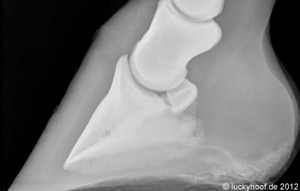

Rechts ein gesunder Huf Links unten extreme Hufrehe, kurz vorm  Sohlendurchbruch (großer Pfeil) Rechts unten: Das Pferd hatte eine Rehe mit einer Hufbeinrotation, ist in Panik geraten, ausgebrochen und einige Kilometer galoppiert. Das Resultat ist eine zusätzliche Hufbeinabsenkung mit einer deformierten, gebrochenen Hufbeinspitze (Pfeil).